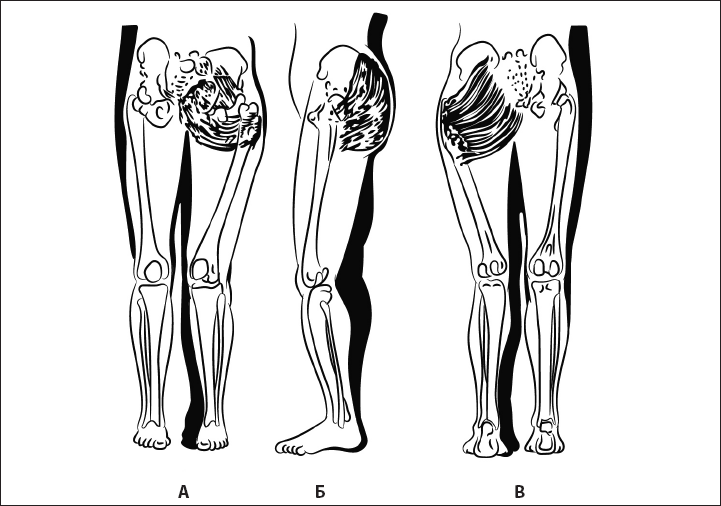

Рис. 32. Укорочение пояснично-подвздошной мышцы. А – вид спереди, Б – вид сбоку, В – вид сзади.

Биомеханика. Коленный сустав в разогнутом состоянии обеспечивает стабилизацию ноги при опоре на нее. Визуальные критерии – разгибание коленного сустава.

Ошибка. Сгибание коленного сустава и опора на полусогнутый сустав. Причина – в гипотонии четырехглавой мышцы бедра и укорочении пояснично-подвздошной мышцы, разгибателей бедра (рис. 32). В результате нарушается стабильность таза и коленного сустава, происходит перегрузка менисков коленного сустава в зависимости от локализации компенсаторно-перегруженной мышцы.

Биомеханика. Тазобедренный сустав сгибается строго по вертикальной линии без отклонений в сторону. Большую роль в его стабилизации в вертикальном положении играет пояснично-подвздошная мышца. В зависимости от ее исходного состояния изменяется нагрузка на сустав (рис. 38, 39) и неправильно формируется его сгибание (рис. 33, 34).

Ошибка 1. Сгибание в суставе сочетается с наружным разворотом ноги так, что пальцы стопы смещены кнаружи от пятки. Причина – укорочение пояснично-подвздошной мышцы (рис. 38).

Рис. 38. Экстензия бедра с укорочением пояснично-подвздошной мышцы. А – вид сзади, Б – вид сбоку.

Ошибка 2. Вместо сгибания в тазобедренном суставе происходит сгибание в коленном или поясничном регионе; пальцы стопы относительно пятки смещаются вовнутрь. Причина – гипотония пояснично-подвздошной мышцы (рис. 39).

Ошибка 3. Сгибание ноги сопровождается разворотом таза.

Рис. 39. Гипотония пояснично-подвздошной мышцы. А – вид спереди, Б – вид сбоку, В – вид сзади.

Рис. 43. Гипотония большой ягодичной мышцы. А – вид спереди, Б – вид сбоку, В – вид сзади.